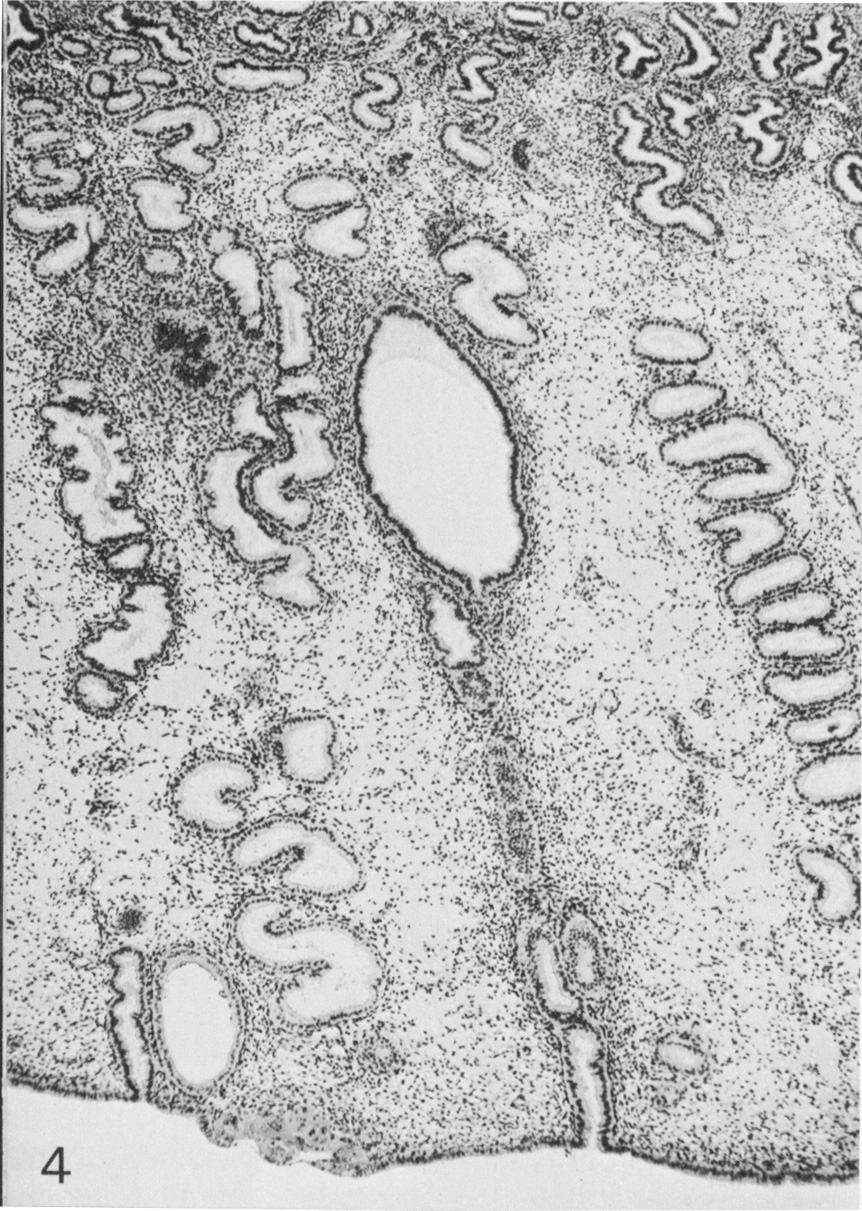

General view of the tissues at and near the implantation site. The endometrium is edematous.

Fig. 4. O'Rahilly and Müller, 1987.

Keywords: edematous endometrial stroma (decidua), endometrium, implantation site

Source: The Virtual Human Embryo.